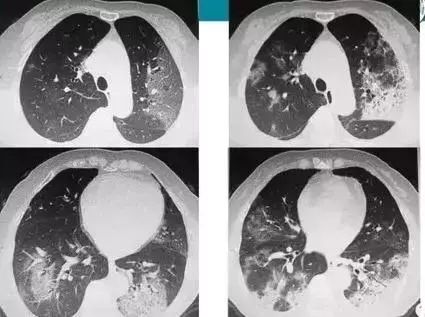

腺病毒最典型的重症,就是腺病毒肺炎了!

【连载】小儿肺炎的热点问题研究-3小儿腺病毒肺炎